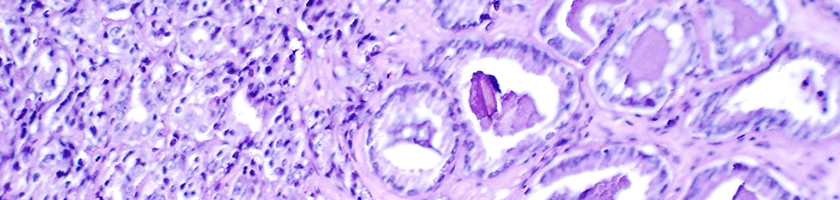

Diagnosing Prostate Cancer

To diagnose prostate cancer, a doctor my perform a digital rectal exam and order a prostate-specific antigen (PSA) blood test. While these tests may indicate a problem with the prostate, a doctor will order a transrectal ultrasound and transrectal biopsy to confirm.